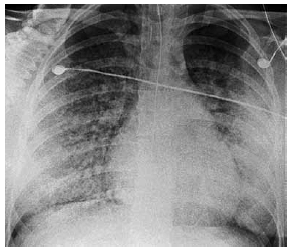

Mulher de 53 anos de idade, etilista, apresenta quadro de vômitos intensos há 2 dias, com provável aspiração orotraqueal. Em seguida, evolui com dispneia intensa, agitação, confusão e cianose de extremidades. Exame clínico: PA: 115 x 65 mmHg, FC: 128 bpm, FR: 44 ipm, T: 36,3 ºC, e SatO2: 54%; ausculta pulmonar com roncos e estertores difusos. A radiografia realizada é mostrada a seguir.